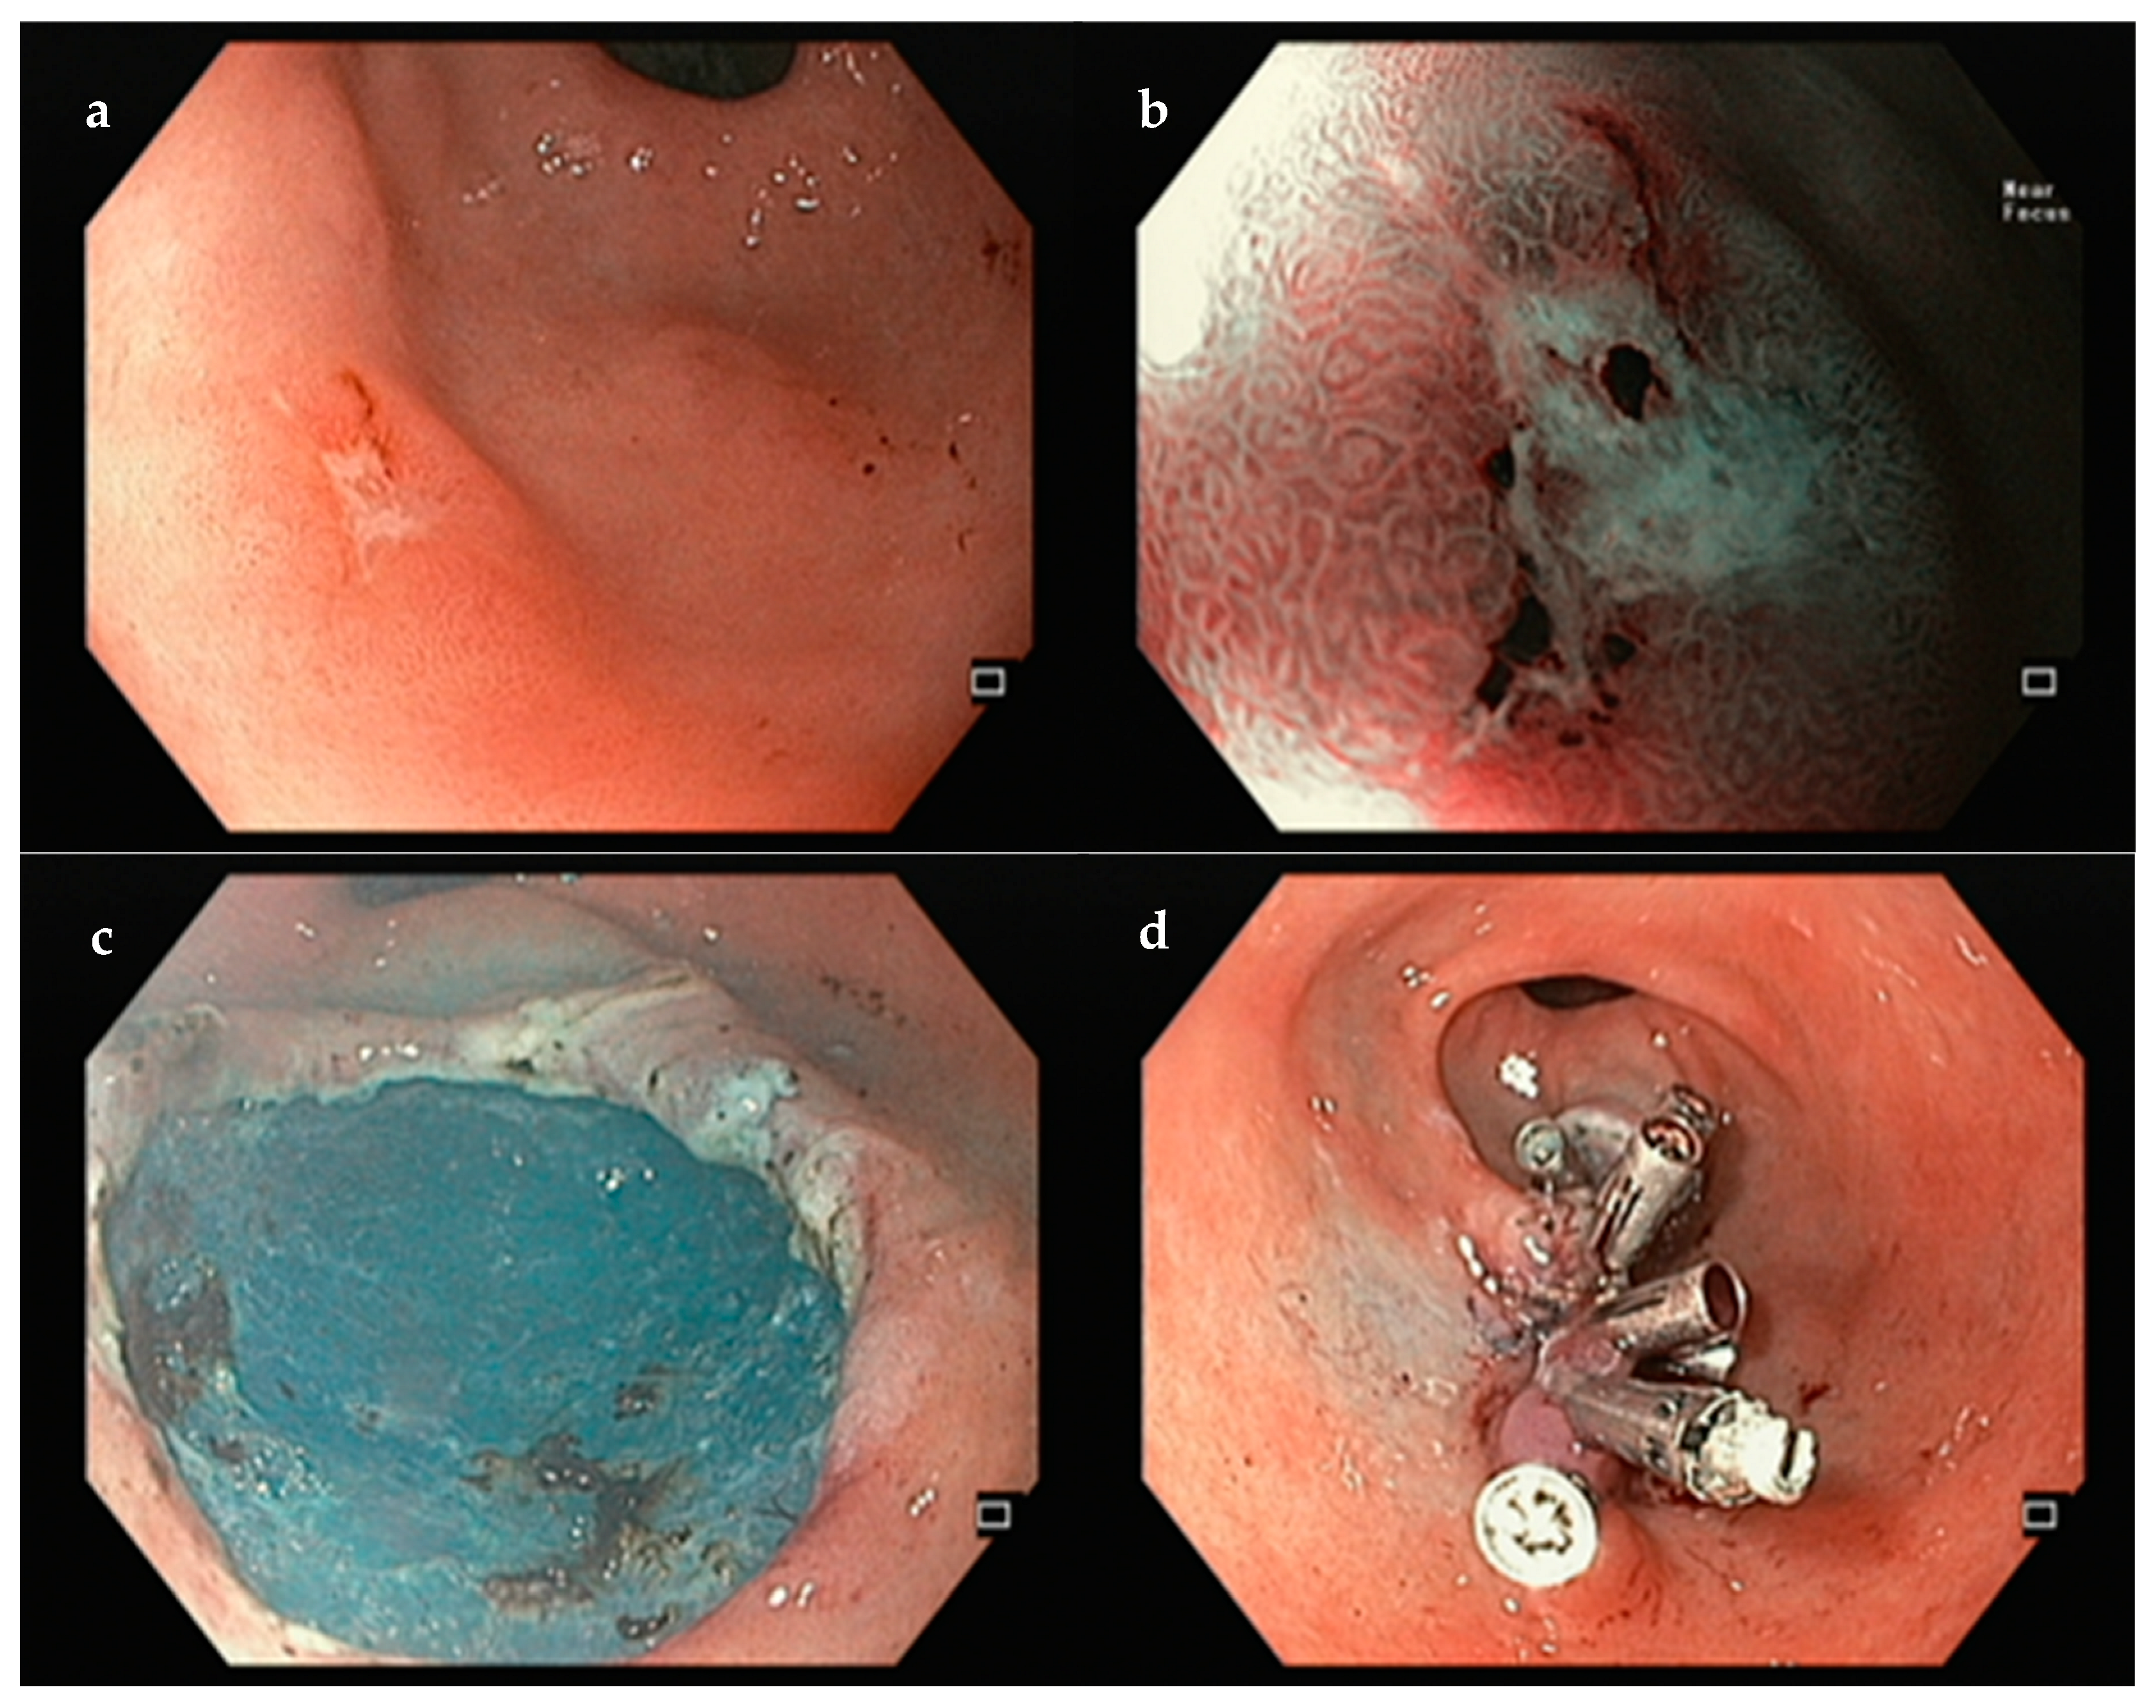

3.2. Stomach